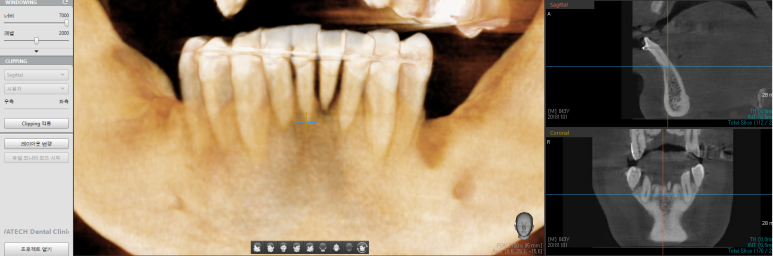

실제 환자의 구강스캔 사진과 CT를 바탕으로 한 모의식립사진입니다.

아직 식립하지 않았지만 어떤 결과가 나올지 예측하여 환자와 모의 결과물로 상담이 가능합니다.

위는 환자의 디오 임플란트 3shape Implant studio에서 보내온

해당 환자의 레포트로 내용 캡쳐부분은 생략하였습니다.